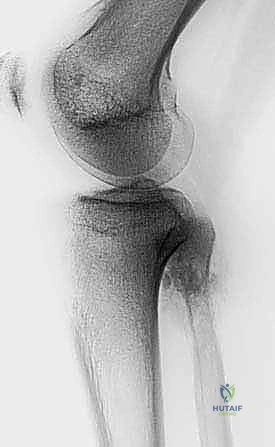

- الأشعة السينية (X-rays): الخطوة الأولى. تظهر التغيرات في الهيكل العظمي، تآكل العظم، أو التفاعلات السمحاقية (Periosteal reaction) التي تدل على وجود ورم.

- التصوير بالرنين المغناطيسي (MRI): المعيار الذهبي. يوضح بدقة متناهية امتداد الورم داخل نخاع العظم، وحجم الكتلة في الأنسجة الرخوة المحيطة، وعلاقة الورم بالأعصاب والأوعية الدموية.

- التصوير المقطعي المحوسب (CT Scan): ممتاز لتقييم التفاصيل الدقيقة للقشرة العظمية واكتشاف أي تكلسات داخل الورم.